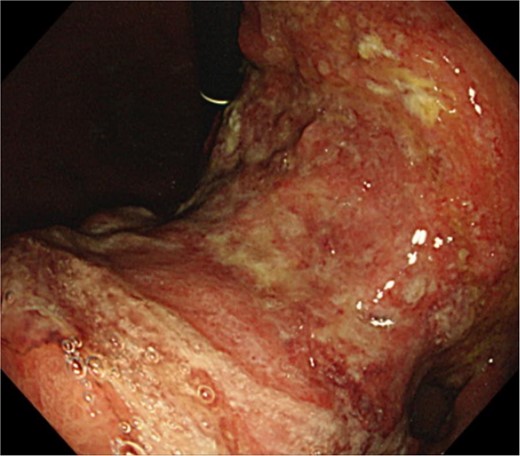

An 83-year-old man visited due to discomfort in the stomach. The patient underwent upper endoscopy that revealed a large tumor in the stomach (Fig. 1). The histological diagnosis was moderately differentiated tubular adenocarcinoma. Computed tomography (CT) revealed thickening of the gastric wall and bulky lymph nodes around the pancreas (Fig. 2). The patient underwent subtotal gastrectomy with Roux-en-Y reconstruction. The metastatic lymph nodes around the pancreas were removed. Abdominal drainage from Winslow’s foramen was performed. The pathological result was pT4aN3aM0 and Stage IIIB [1].

Clinical findings of endoscopy. Upper endoscopy showing a large tumor from body to antrum of the stomach.